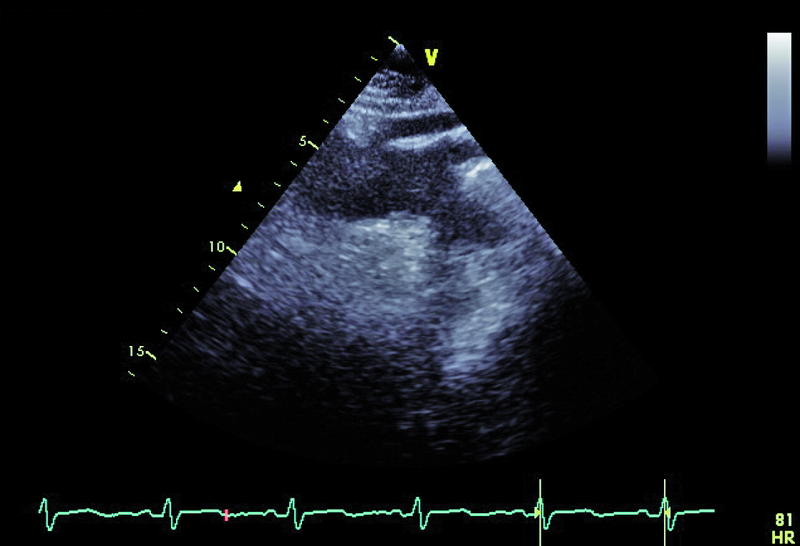

Pacjent, lat 60, z wywiadem nadciśnienia tętniczego, wieloletni palacz, został przyjęty do kliniki w celu oceny układu krążenia po przebytym rok wcześniej udarze mózgu. W przebiegu udaru obserwowano afazję ruchową, niedowład centralny nerwu VII, niedowład prawej kończyny górnej. Chory był intensywnie rehabilitowany, co przyczyniło się do stopniowego ustąpienia zaburzeń mowy oraz istotnej poprawy ruchomości prawej kończyny górnej. W tomografii komputerowej stwierdzono obszar hipodensyjny na pograniczu płata ciemieniowego i potylicznego lewej półkuli mózgu. Spektralne badanie doplerowskie tętnic szyjnych i kręgowych nie wykazało istotnych hemodynamicznie zaburzeń przepływu. Opiekujący się pacjentem neurolodzy podejrzewali, że przyczyną udaru mógł być przetrwały otwór owalny (patent foramen ovale, PFO). W wykonanych w klinice badaniach echokardiograficznych – przezklatkowym i przezprzełykowym – przegroda międzyprzedsionkowa była szczelna. Jama lewej komory była niepowiększona, a grubość mięśnia graniczna. Zwracało uwagę nieznaczne upośledzenie kurczliwości mięśnia komory (EF=50%) oraz poszerzenie aorty do 42 mm.

Wiek pacjenta, palenie tytoniu oraz chwiejne nadciśnienie tętnicze nakazują wykluczyć a priori tzw. kryptogenny udar mózgu. Przegroda międzyprzedsionkowa u chorego była szczelna, choć w badaniu przezprzełykowym (TOE) opisano śladowy kanał przetrwałego otworu owalnego (PFO), bez przechodzenia kontrastu ze strony prawej na lewą. Badanie przezprzełykowe pozwoliło także wykluczyć skrzeplinę w jamach serca (ryc. 1 – uszko lewego przedsionka) oraz istotne zmiany organiczne zastawki aortalnej (ryc. 2, 3). Prawdopodobną przyczyną udaru były nasilone zmiany miażdżycowe w łuku aorty z towarzyszącymi owrzodzeniami ściany naczynia (ryc. 4, 5). Warto zaznaczyć, że zmiany będące zgrubieniem błony wewnętrznej bywają dynamiczne i nie można wykluczyć powstawania ruchomych składowych (skrzeplin) na dużych elementach owrzodzenia. W diagnostyce miażdżycowego uszkodzenia aorty metodą z wyboru jest badanie przezprzełykowe, pozwalające zidentyfikować dzięki wysokiej rozdzielczości obrazu drobne, nawet kilkumilimetrowe owrzodzenia. Warto zaznaczyć, że badanie przezklatkowe nie dostarcza tak wyraźnego i jednoznacznego obrazu (ryc. 6). Korzyść z badania echokardiograficznego jest bez wątpienia większa niż z badania TK czy MR, ze względu na możliwość oceny ruchomości blaszek w czasie rzeczywistym. W rutynowej ocenie zwraca się uwagę na grubość blaszki miażdżycowej, obecność owrzodzeń, zwapnień oraz nałożonych ruchomych ech odpowiadających skrzeplinom – stanowiących tzw. potencjał zatorowy blaszki. Uważa się, że średnica blaszki przekraczająca 4 mm ma większy potencjał zatorowy niż owrzodzenie płytkie (w przedstawionym przypadku średnica blaszki wynosiła 7 mm). Dowiedziono ponadto, że w przypadku blaszek nieuwapnionych – jak w opisanej sytuacji – ryzyko zatoru jest większe niż w przypadku blaszek uwapnionych. Leczenie antykoagulacyjne w takim wypadku jest uzasadnione. Konieczne jest także włączenie dużej dawki statyn mimo braku zmian miażdżycowych w tętnicach wieńcowych (wykonano koronarografię). Ocena układu krążenia u pacjenta po przebytym incydencie zatorowym do OUN powinna być kompleksowa i powinna uwzględniać wszystkie możliwe nieprawidłowości.